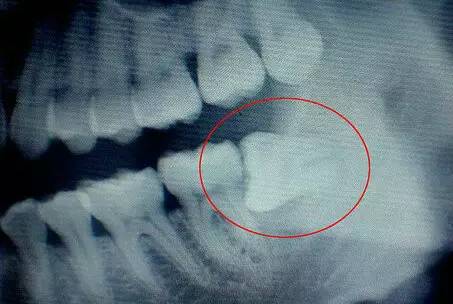

B:造成邻牙病变:邻牙病变的患者通常没有感觉,大多由牙医以X光诊断发现。这是由于智齿萌出的空间不足,异位阻生斜靠在第二磨牙上,造成第二磨牙清洁不易,甚至是第二磨牙部分被吸收的现象,严重时会引发不舒适或疼痛。

C:智齿阻生:通常这是最麻烦的一种。这一种类型的牙齿,通常埋在齿槽骨的里面,如果经常发生炎症,或是诊断会有病灶发生的时候,就必须拔除。